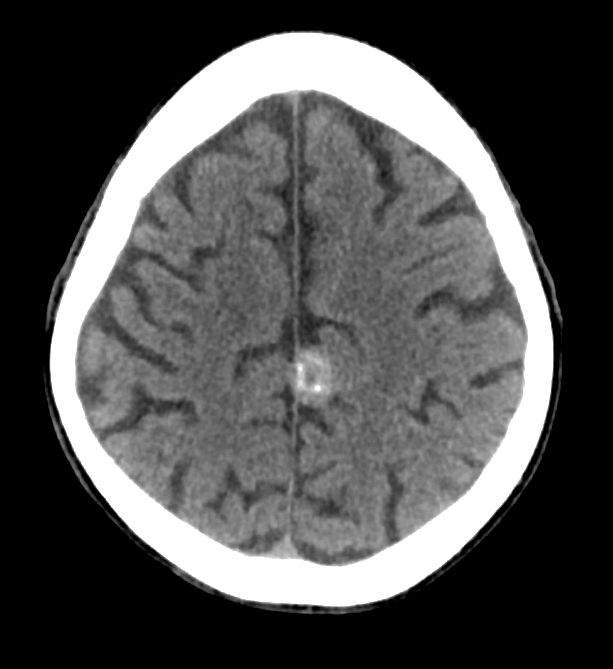

See below for a representative head CT.

Based on the CT scan shown above, which of the following are true? (scroll down for the answer)

- The lesion is EXTRA-AXIAL

- The lesion is INTRA-AXIAL

- The lesion is MALIGNANT

- The lesion is HEMORRHAGIC

The answer is 2) the lesion is extra-axial. Take a look at the brain MRI’s below to prove it to yourself.